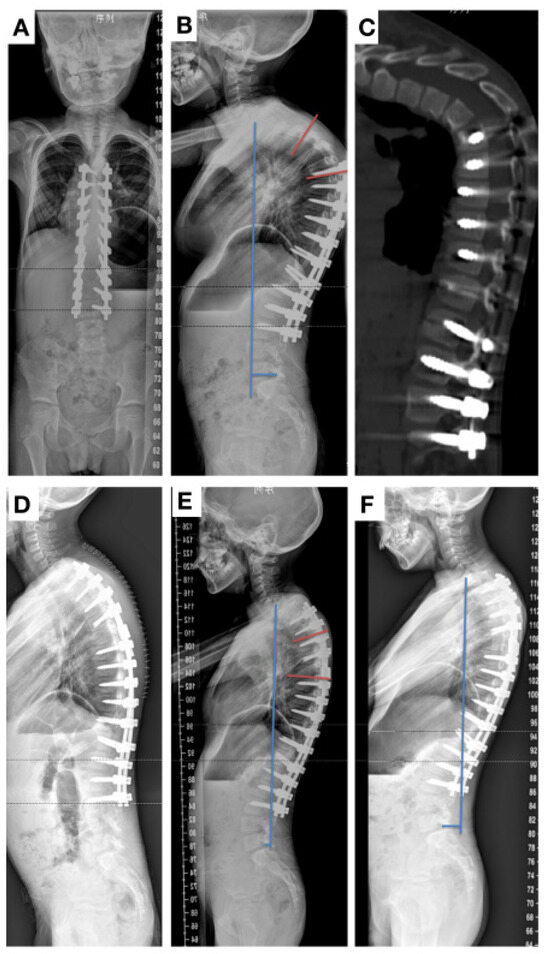

2. Case Presentation